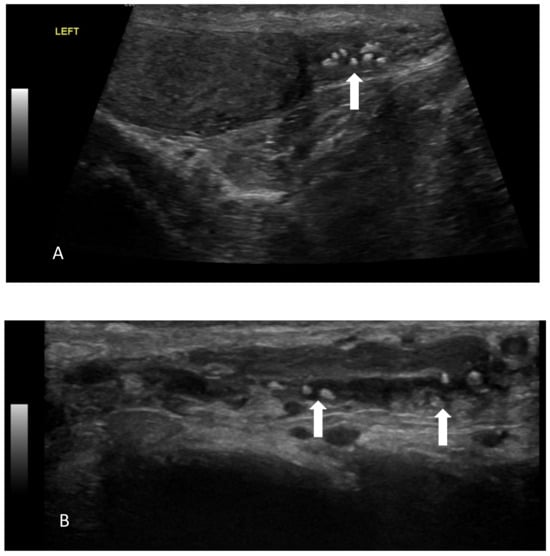

- A case of a patient with AIP type 1 and other organ involvement (bile ducts, testicles, nasal polyps, and lungs) is described.

5.1. AIP Type 1 and Testicular Involvement